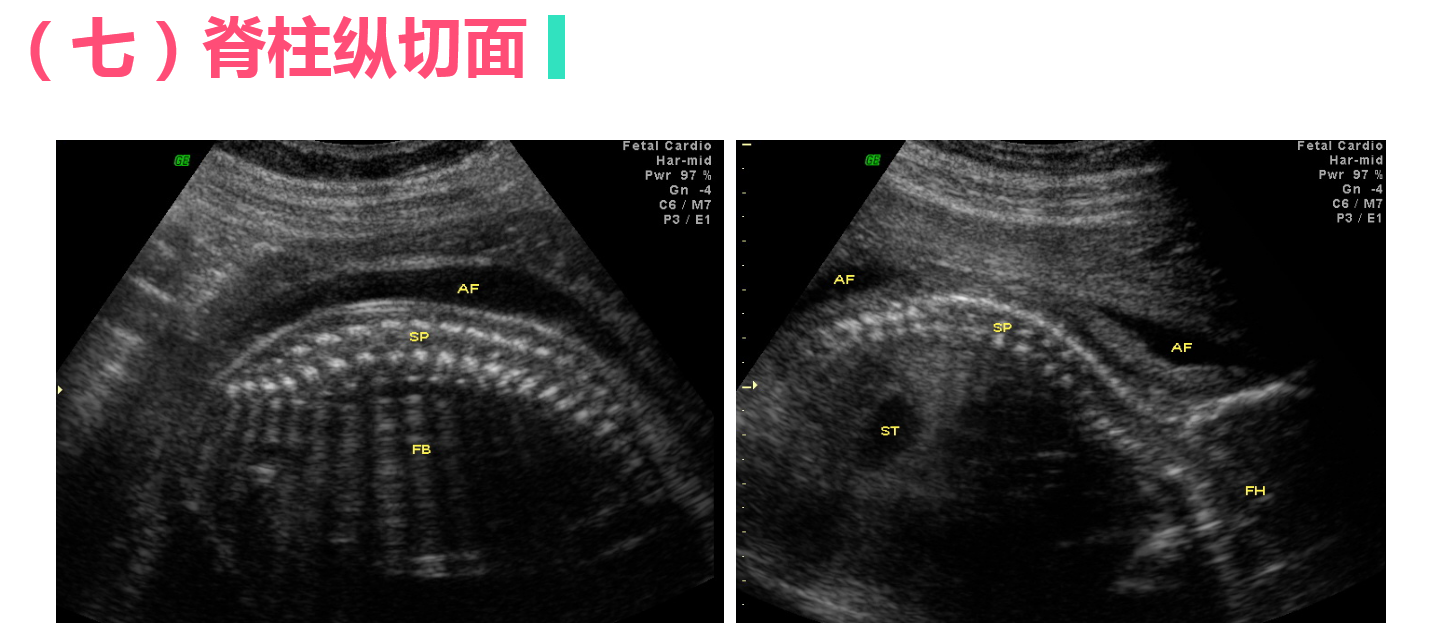

正常中晚期妊娠声像图

• 4.4 异常妊娠声像图